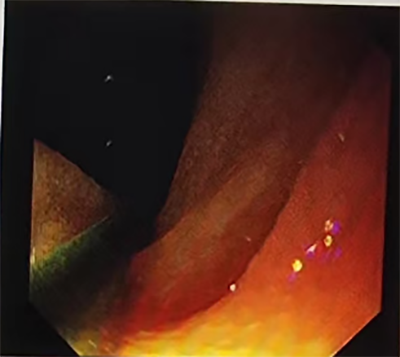

消化科副主任医师李涛副凭借丰富的消化介入经验,无需X线引导,将不需异物钳配合的经鼻超细胃镜经患者右侧鼻腔缓缓进入,抵达十二指肠远端。随后,通过活检通道送入导丝至门齿100cm,固定导丝后小心撤出超细胃镜,由助手丰丙程主治医师协助固定导丝,经导丝将肠梗阻导管顺利送达距门齿 90cm 处。为确保导管位置准确且功能正常,再经左侧鼻腔进超细胃镜至前球囊处,在直视下注入纯净水15ml观察到导管前端球囊扩张。随后撤镜、撤出导丝,局部体外固定导管。